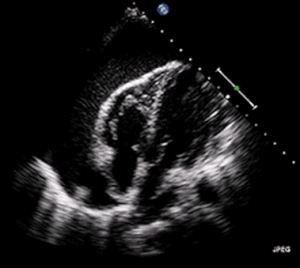

Echocardiogram (ultrasound): when pericardial effusion is suspected, echocardiography usually confirms the diagnosis and allows assessment of the size, location and signs of hemodynamic instability.[5] A transthoracic echocardiogram (TTE) is usually sufficient to evaluate pericardial effusion and it may also help distinguish pericardial effusion from pleural effusion and MI. Most pericardial effusions appear as an anechoic area (black or without an echo) between the visceral and the parietal membrane.[1] Complex or malignant effusions are more heterogeneous in appearance, meaning they may have variations in echo on ultrasound.[4] TTE can also differentiate pericardial effusion based on the size. Although it's difficult to define size classifications because they vary with institutions, most commonly they are as follows: small <10, moderate 10-20, large >20. [4]An echocardiogram is urgently needed for evaluation when there is concern for hemodynamic compromise, a rapidly developing effusion or history of recent cardiac surgery/procedures.[1]

A large anechoic (black) pericardial effusion as seen on ultrasound. Closed arrow: the heart, open arrow: the effusion